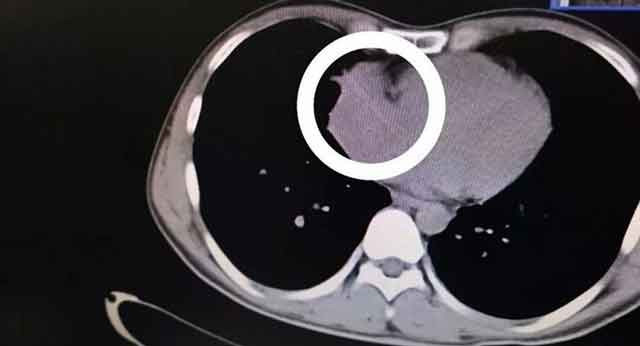

Çin'de doktorlar Zhou soyadlı bir hastanın kalp atışlarındaki dengesizliği araştırırken, tesadüf eseri sağ kalp kapakçığında sivri uçlu bir nesne tespit etti. Kürdan olduğu anlaşılan nesnenin kalbe nasıl girdiğini duyunca şoke olacaksınız.

Akıl almaz olay Çin'in Guangksi Zhuang Özerk Bölgesi'ndeki Nanning kentinde yaşandı. 4 yıl önce alkol alırken yuttuğu kürdan Zhou soyadlı adamın kalbine saplandığı anlaşıldı. Doktorları bile dehşete düşüren olay sonrası kürdan 7 saatlik ameliyat sonrası çıkartıldı. Adamın yuttuğu kürdan ise bakın kalbine nasıl gitmiş.

Çin'de bir hastanın kalbinden, 4 yıl önce alkol tüketirken yuttuğunu iddia ettiği bir kürdan çıkartıldı. Guangksi Zhuang Özerk Bölgesi'ndeki Nanning kentinin cerrahları, bu akıl almaz durumla 9 Ocak tarihinde gerçekleştirdikleri açık kalp ameliyatı esnasında karşı karşıya kaldı.